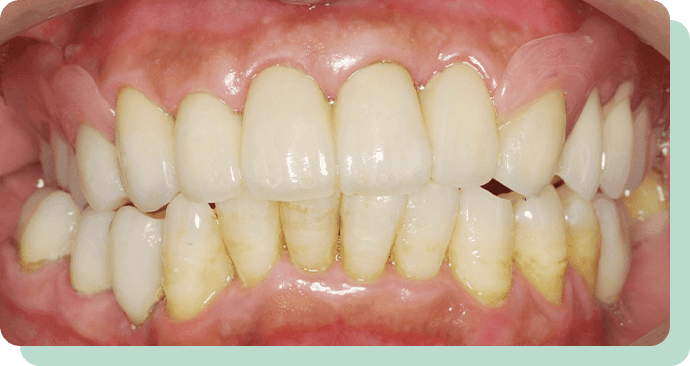

処置前後

この方は、歯を短くし、金属のキャップの上に特殊な入れ歯を装着。

これにより、快適にお食事ができるようになりました。

リスク:疼痛・咬合時痛・冷水痛・出血・歯ぐきへの損傷

費用:金属床義歯使用 280,000円